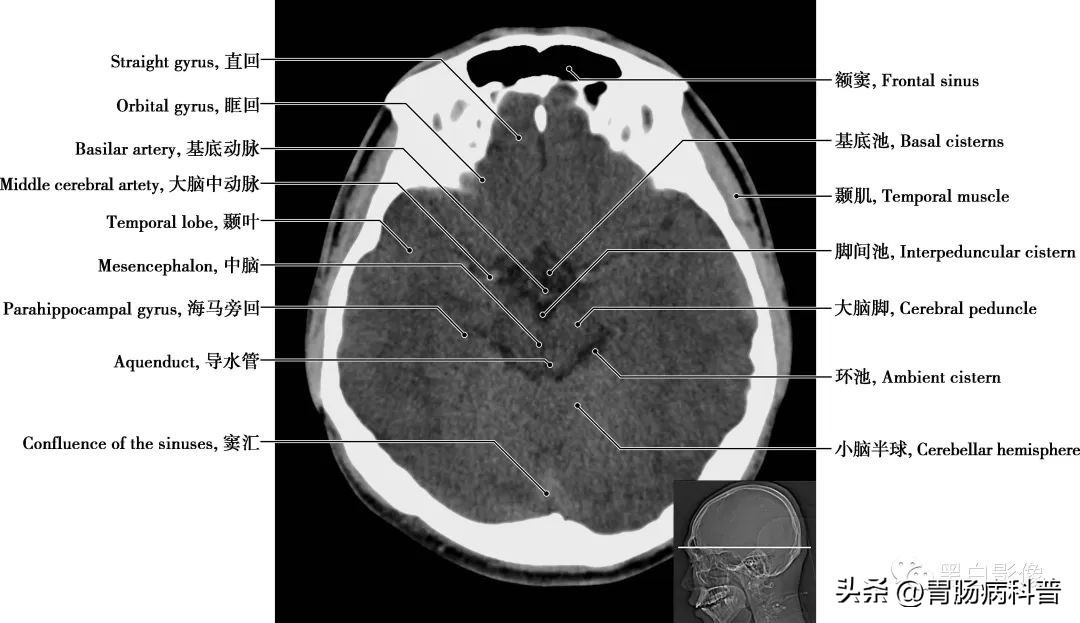

图1-1-12 经脑桥轴位切面

第四脑室 位于小脑、延髓和脑桥间,上接中脑导水管,下通脊髓中央管。接受第三脑室的脑脊液,并通过中孔或侧孔流向蛛网膜下腔,进入静脉系统。底部呈菱形,脑桥与延髓的神经核团多与此相毗邻。小脑半球 按功能可分为:前庭小脑,调整肌紧张,维持身体平衡;脊髓小脑,控制肌肉的张力和协调;大脑小脑,影响运动的起始、计划和协调